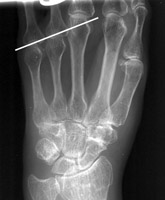

Short 4th Metacarpal

Radiograph of the hand which reveals an abnormally short 4th metacarpal, as compared to the other metacarpal bones. Although this sign usually is associated with Turner's syndrome, the short 4th "metacarpal sign" carries a short differential diagnosis and is therefore not pathognomonic.